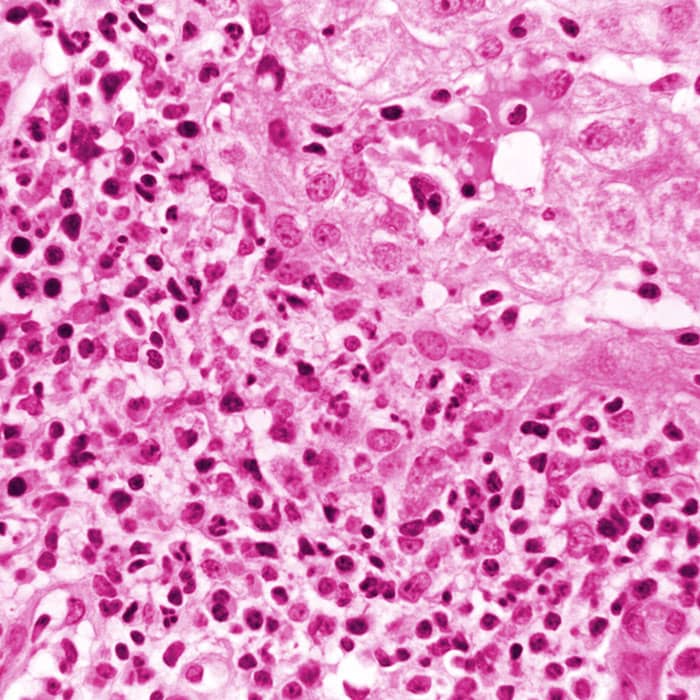

In the study, publishing on March 30 in Nature, researchers linked the disease to co-infections from multiple common viruses, in particular a strain of adeno-associated virus type 2 (AAV2). AAVs are not known to cause hepatitis on their own. They need “helper” viruses, such as adenoviruses that cause colds and flus, to replicate in the liver.

Since AAVs are not considered pathogenic on their own, a direct causal link with the severe acute hepatitis has yet to be established. The study notes, however, that children may be especially vulnerable to more severe hepatitis triggered by co-infections. While infections from adeno-associated viruses can occur at any age, the peak is typically between 1 and 5 years old, and the median age of the affected children in the study was 3 years old.